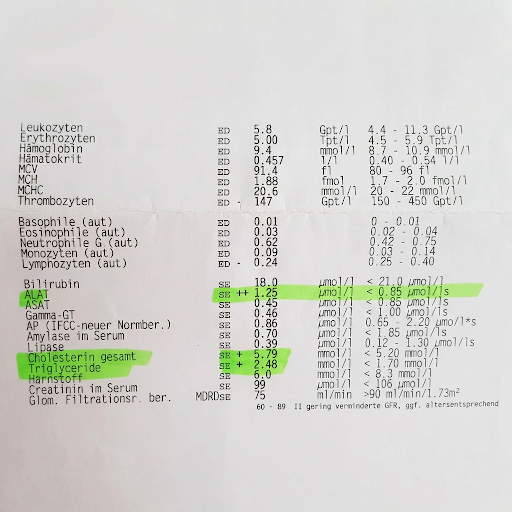

Mein Arzt schaute auf den Bildschirm. „Gamma-GT bei 89. GPT bei 68. Das ist fast das Doppelte vom Normalwert.“

Nach 6 Wochen machte ich ein neues Blutbild.

Das Ergebnis? Ernüchternd.

Mein Gamma-GT wurde minimal besser meine GPT- Werte so gut wie gar nicht.

Nach 8 Wochen hatte ich 4 Kilo verloren. Aber meine Leberwerte? Nur 5% besser.

Woche 8: Der Bluttest

Ich hatte einen Termin bei meinem Hausarzt. Kontroll-Blutbild. Ich war nervös. Was, wenn sich nichts verändert hatte? Denn ich fühlte mich wirklich um einiges besser!

Zwei Tage später rief er an.

„Michael, ich habe deine Werte. Und ich muss dich mal fragen – was hast du gemacht?“

Gamma-GT: Von 89 auf 42. GPT: Von 68 auf 34. Beides im Normalbereich.

Und der Ultraschall-Termin kam…

6 Monate später: Ich mache es kurz…

Ich lag auf der Liege. Er fuhr mit dem Gerät über meinen Bauch. Schaute auf den Bildschirm. Runzelte die Stirn.

„Interessant.”, in so einem komischen Ton. Und dann sagte er:

„Jetzt sehe ich einzelne kleine Verfettungen. Aber fast nicht mehr messbar. Ich würde sagen: Grad 0,5 bis 1.“

Er schaute mich an. „In 6 Monaten von Grad 2 auf fast normal. Das ist unglaublich.“